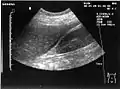

Ultrasound of liver (left side of the image) and right kidney (right side of the image) and Morison's pouch, not containing fluid.